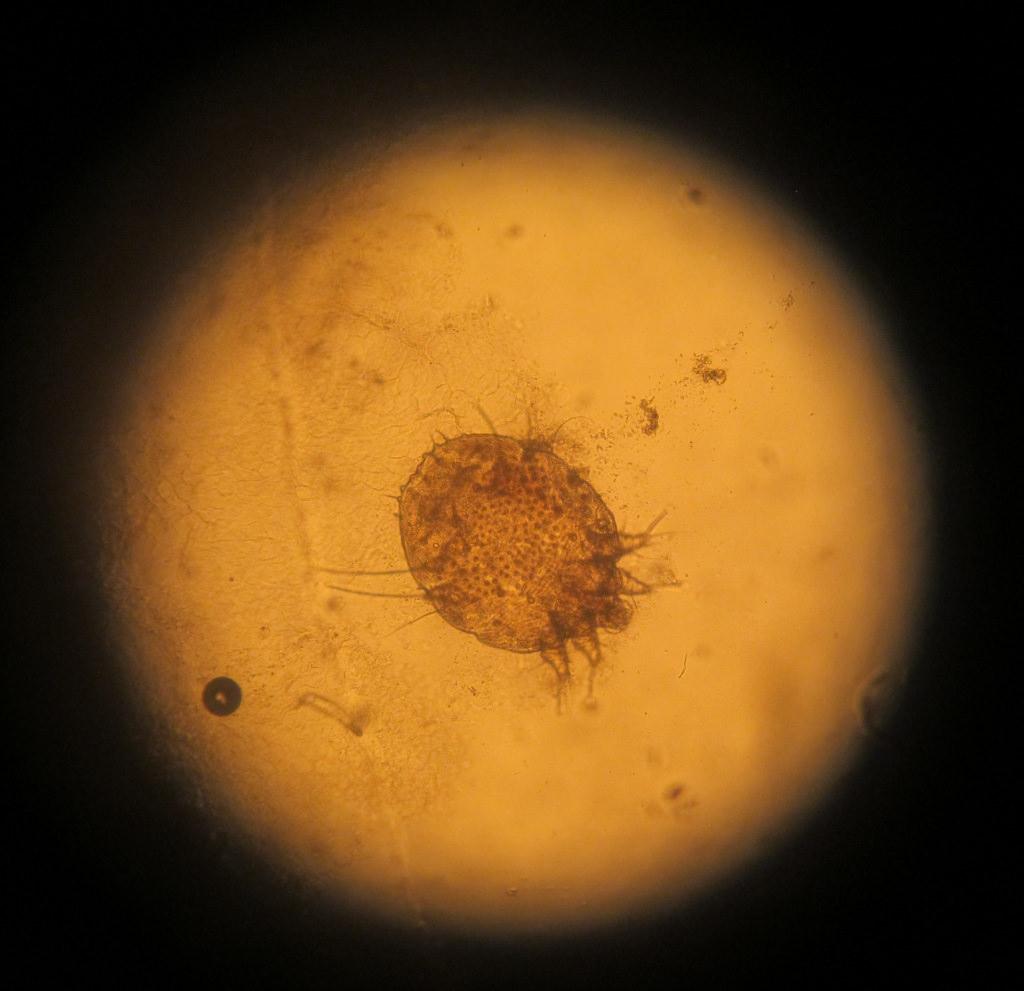

как выглядит чесоточный клещ

Заражение осуществляют самки и личинки. Самка обитает в коже. В дневное время она неактивна, но вечером она активно прогрызает ходы, размножается, питается и выделяет продукты переработки. Следовательно, самый большой риск заразиться появляется именно в вечернее-ночное время, когда клещ проявляет большую активность.

Клеща можно обнаружить с помощью молочной кислоты. Одну каплю (40%) нужно нанести на любое поражение и подождать 5 минут. После разрыхленную кожу можно соскоблить острой ложкой, пока не появится капиллярное кровотечение. Полученный эпидермис нужно нанести на предметное стекло и посмотреть на него под микроскопом. Метод позволит определить большинство паразитов и продуктов их активности.